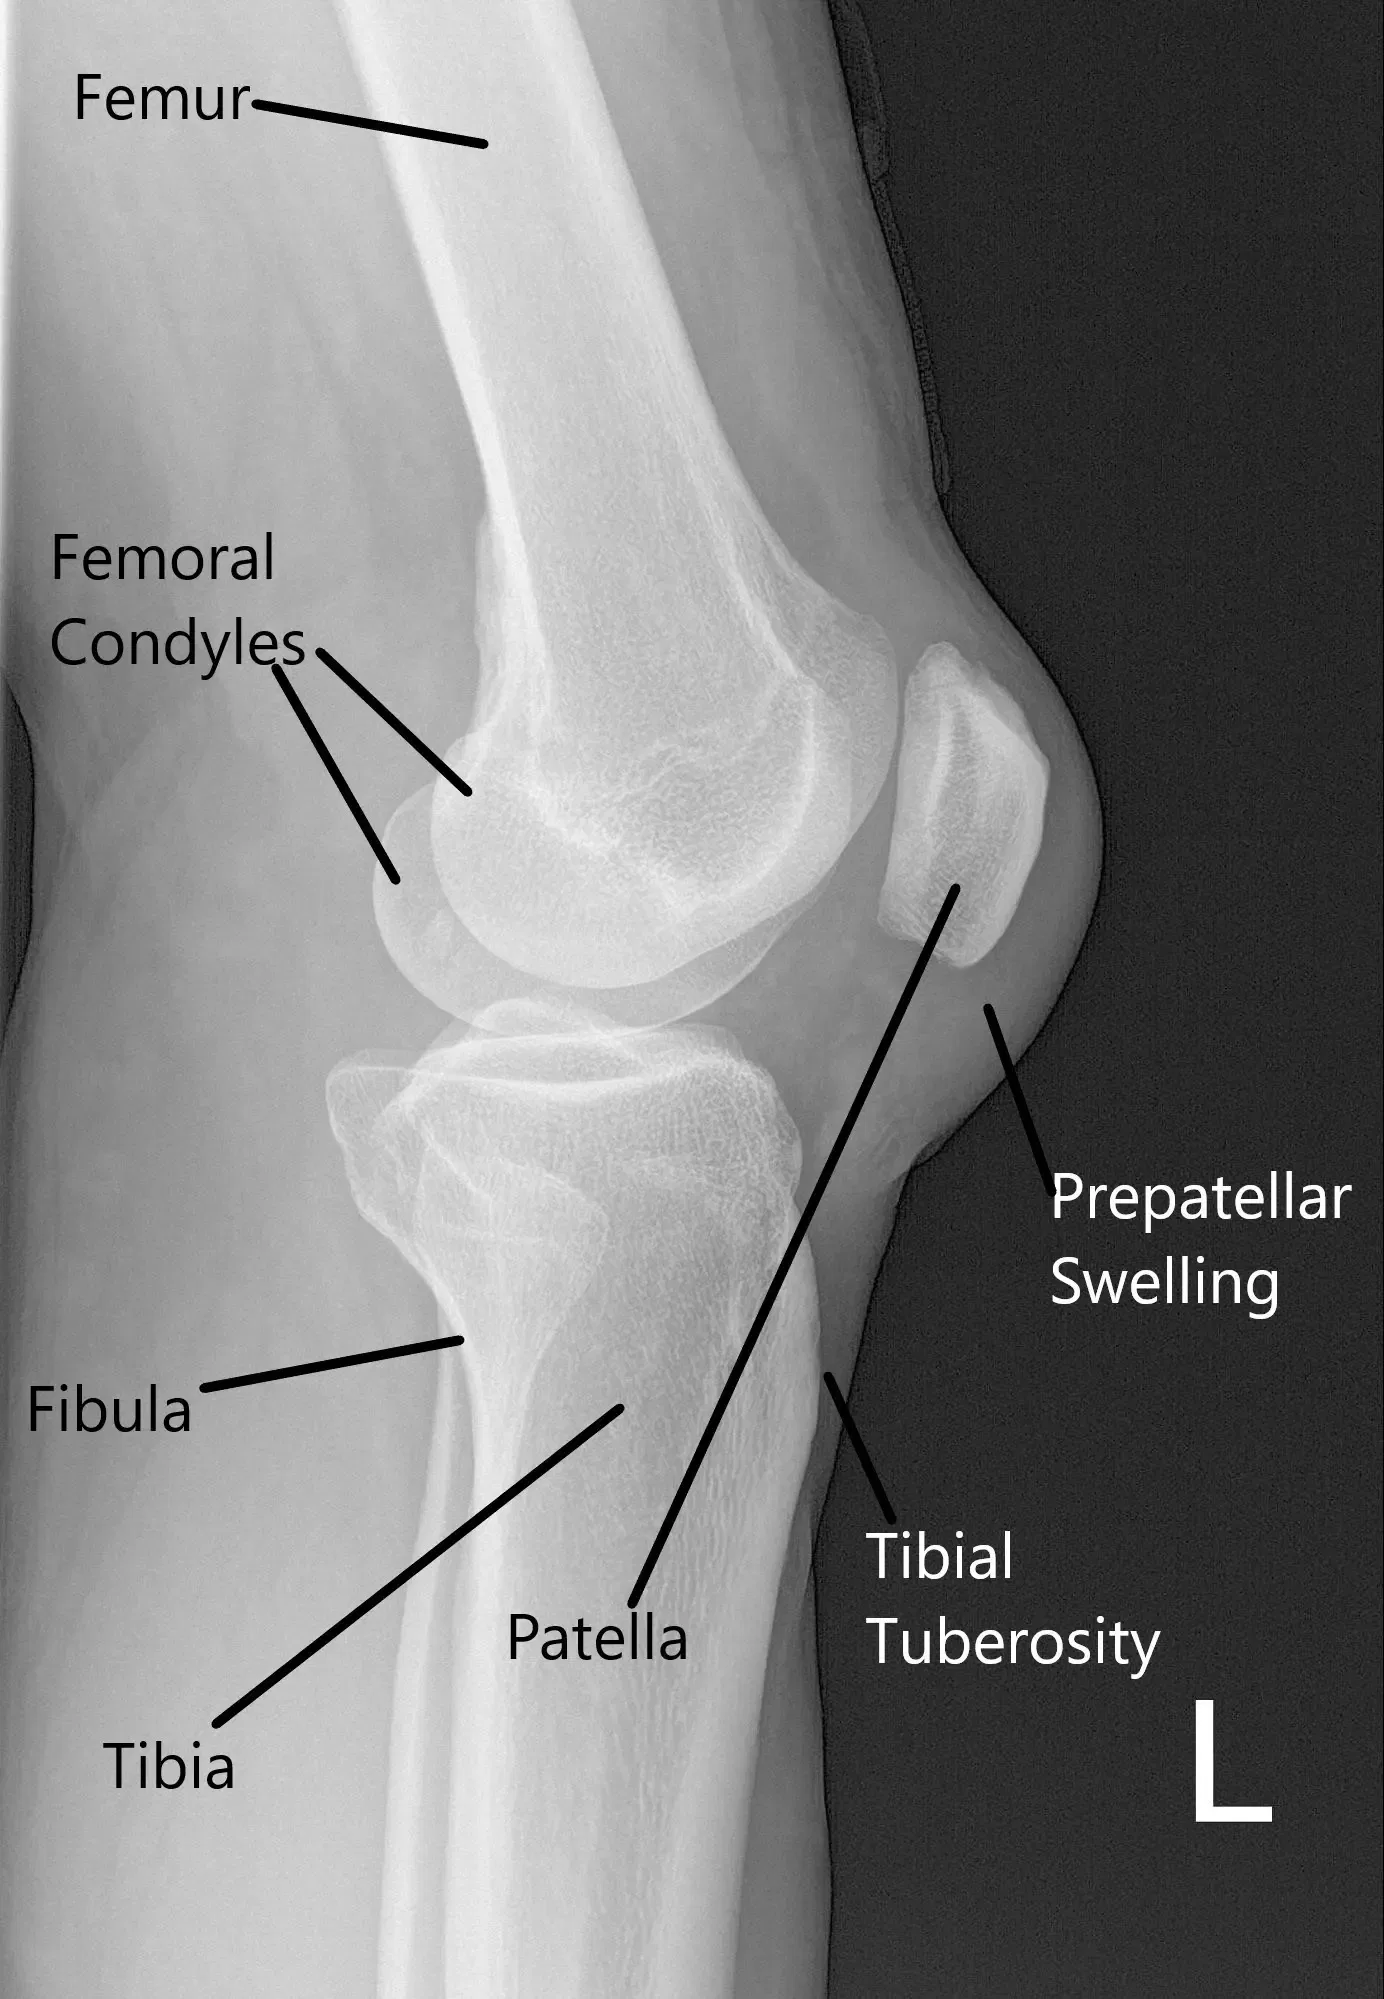

La radiografía de la rodilla izquierda indicó hinchazón de tejidos blandos por delante de la rótula y la inclinación de la rótula.

Radiografía de la rodilla izquierda en vista lateral.